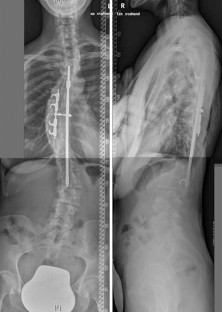

Abb. 2

Ziel der vorliegenden Studie ist es, den Effekt verschiedener dorsaler Operationstechniken auf das sagittale Profil zu untersuchen. Retrospektiv wurden 36 Patienten mit thorakaler idiopathischen Adoleszentenskoliose eingeschlossen, welche mittels dorsaler Korrekturspondylodese versorgt wurden. Unter Berücksichtigung verschiedener Korrekturprinzipien wurden die Patienten in Subgruppen eingeteilt (A Pedikelschraube, B Langkopfpedikelschraube, C Langkopfpedikelschraube mit Ponte-Osteotomien). Standardröntgenaufnahmen der ganzen Wirbelsäule im Stehen wurden vor und mindestens 2 Jahre nach dorsaler Korrektur angefertigt. Eine Subgruppenanalyse wurde zur Detektierung von Gruppenunterschieden vorgenommen.

The purpose of this study was to evaluate the effects of different posterior correction techniques on sagittal profile and balance. A total of 36 consecutive patients with thoracic AIS, who were treated with selective thoracic posterior correction were included in this retrospective study. The patients were further assigned to three different subgroups according to different surgical strategies: A: pedicle screws, B: long-head pedicle screws and C: additional Ponte osteotomy. Standardized radiographs in the standing position of the whole spine in two planes were evaluated before and at least 2 years after correction for all patients and a subgroup analysis was done to identify differences between the three groups.

A significant correction of the major curve was achieved in all three groups (p < 0.001). There was a significant difference between the groups with groups B and C showing significantly higher levels of major curve correction in comparison to group A (p < 0.001). Concerning the sagittal profile, there was a significant difference in the development of thoracic kyphosis (TK) and lumbar lordosis (LL). While a significant reduction of TK and LL was found in groups A and B after surgery, a significant increase of TK and LL was noted in group C which was associated with a decrease of pelvic tilt and an increase of sacral slope. The 2-year follow-up showed the lowest ODI-% value only in group C which was positively correlated with reduction in pelvic tilt.